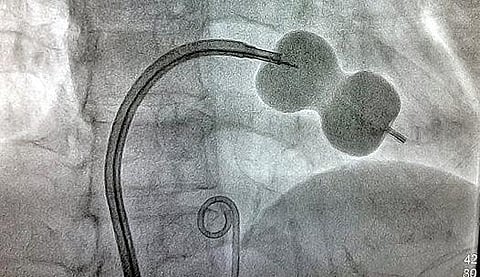

‘ஷீத்’ எனப்படும் உறைக்குள் வைத்து மெல்லிய ஊசியானது தொடையில் உள்ள ரத்தநாளம் வழியாக நோயாளியின் உடலுக்குள் செலுத்தப்பட்டது. அதன்மூலம் இதய நடுதசையில் துளைபோட்டு, சிறிய பலூன் கருவியை எடுத்துச்சென்று இதயத்தின் இடப்பக்க சுருங்கிய வால்வு விரிவுபடுத்தப்பட்டது. முதல்வரின் விரிவான மருத்துவக் காப்பீட்டு திட்டத்தின்கீழ் இலவசமாக இந்த சிகிச்சை மேற்கொள்ளப்பட்டது. இவ்வாறு பலூன் சிகிச்சை அளித்த 24 மணி நேரத்தில் நோயாளிகள் வீட்டுக்குச் சென்றுவிடலாம் என இதயவியல் துறை தலைவர் ஜெ.நம்பிராஜன் தெரிவித்தார்.